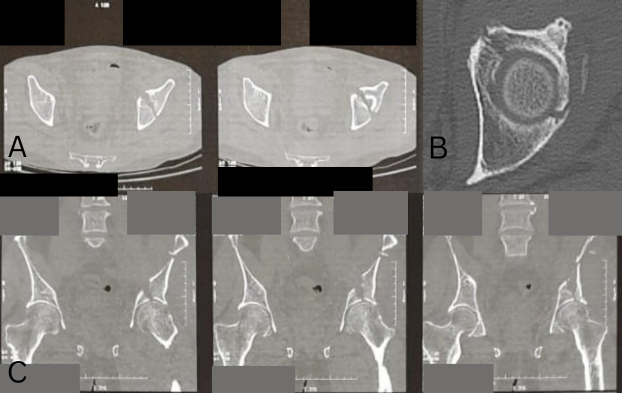

Computed tomography (CT) showed separation of the anterior wall of the cranial fragment by a slightly displaced split line (Fig. 4 and 5).

Figure 4: 3D model reconstruction of superior acetabular fracture (a) Anterior view (b) Posterior view.

Figure 5: Pre-operative computed tomography scan (a) Sagittal view (b) Axial view (c) Coronal view.